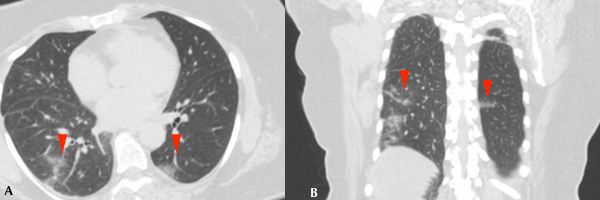

Se realizó TC de tórax a 85 (5,9%) pacientes, de los cuales 11 (13%) fueron positivos por PCR para COVID19. De estos, 9 (81%) manifestaron infiltrados en vidrio esmerilado en el parénquima pulmonar, asociándose además opacidades consolidativas en 4 (36%) de ellos (Figs. 3 y 4). 2 (18%) pacientes no mostraron afectación intersticio-alveolar en su evolución. La TC se realizó a pacientes cuya clínica no era acorde a los hallazgos de Rx y a aquellos con evolución tórpida (81%). En total, a 8 (72%) pacientes COVID-19 positivos se les realizaron ambos métodos imagenológicos.

En cuanto a la distribución, en los cortes axiales se encontró que siete pacientes presentaron opacidades o consolidaciones periféricas, o ambas (Figs. 5 y 6).

En un paciente se encontró patrón en empedrado (Fig. 8) y en dos pacientes opacidades redondeadas en vidrio esmerilado (Tabla 1).